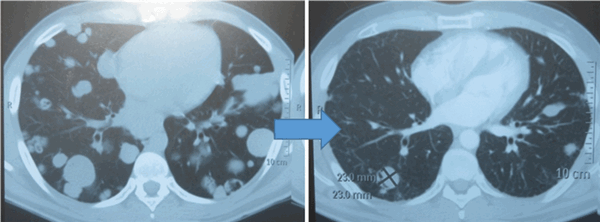

Для оценки эффективности химиотерапии каждые 2 цикла и после ее окончания проводится компьютерная томография исходных зон поражения, перед каждым циклом мониторинг уровня опухолевых маркеров. Рост маркеров на фоне лечения или после его завершения, а также замедление их снижения свидетельствует об активности опухолевого процесса и необходимости проведения второй линии химиотерапии.

![Метастазы в легких до лечения и после 4х циклов химиотерапии по схеме «ВЕР» (КТ грудной клетки)]()

Метастазы в легких до лечения и после 4х циклов химиотерапии по схеме «ВЕР» (КТ грудной клетки)